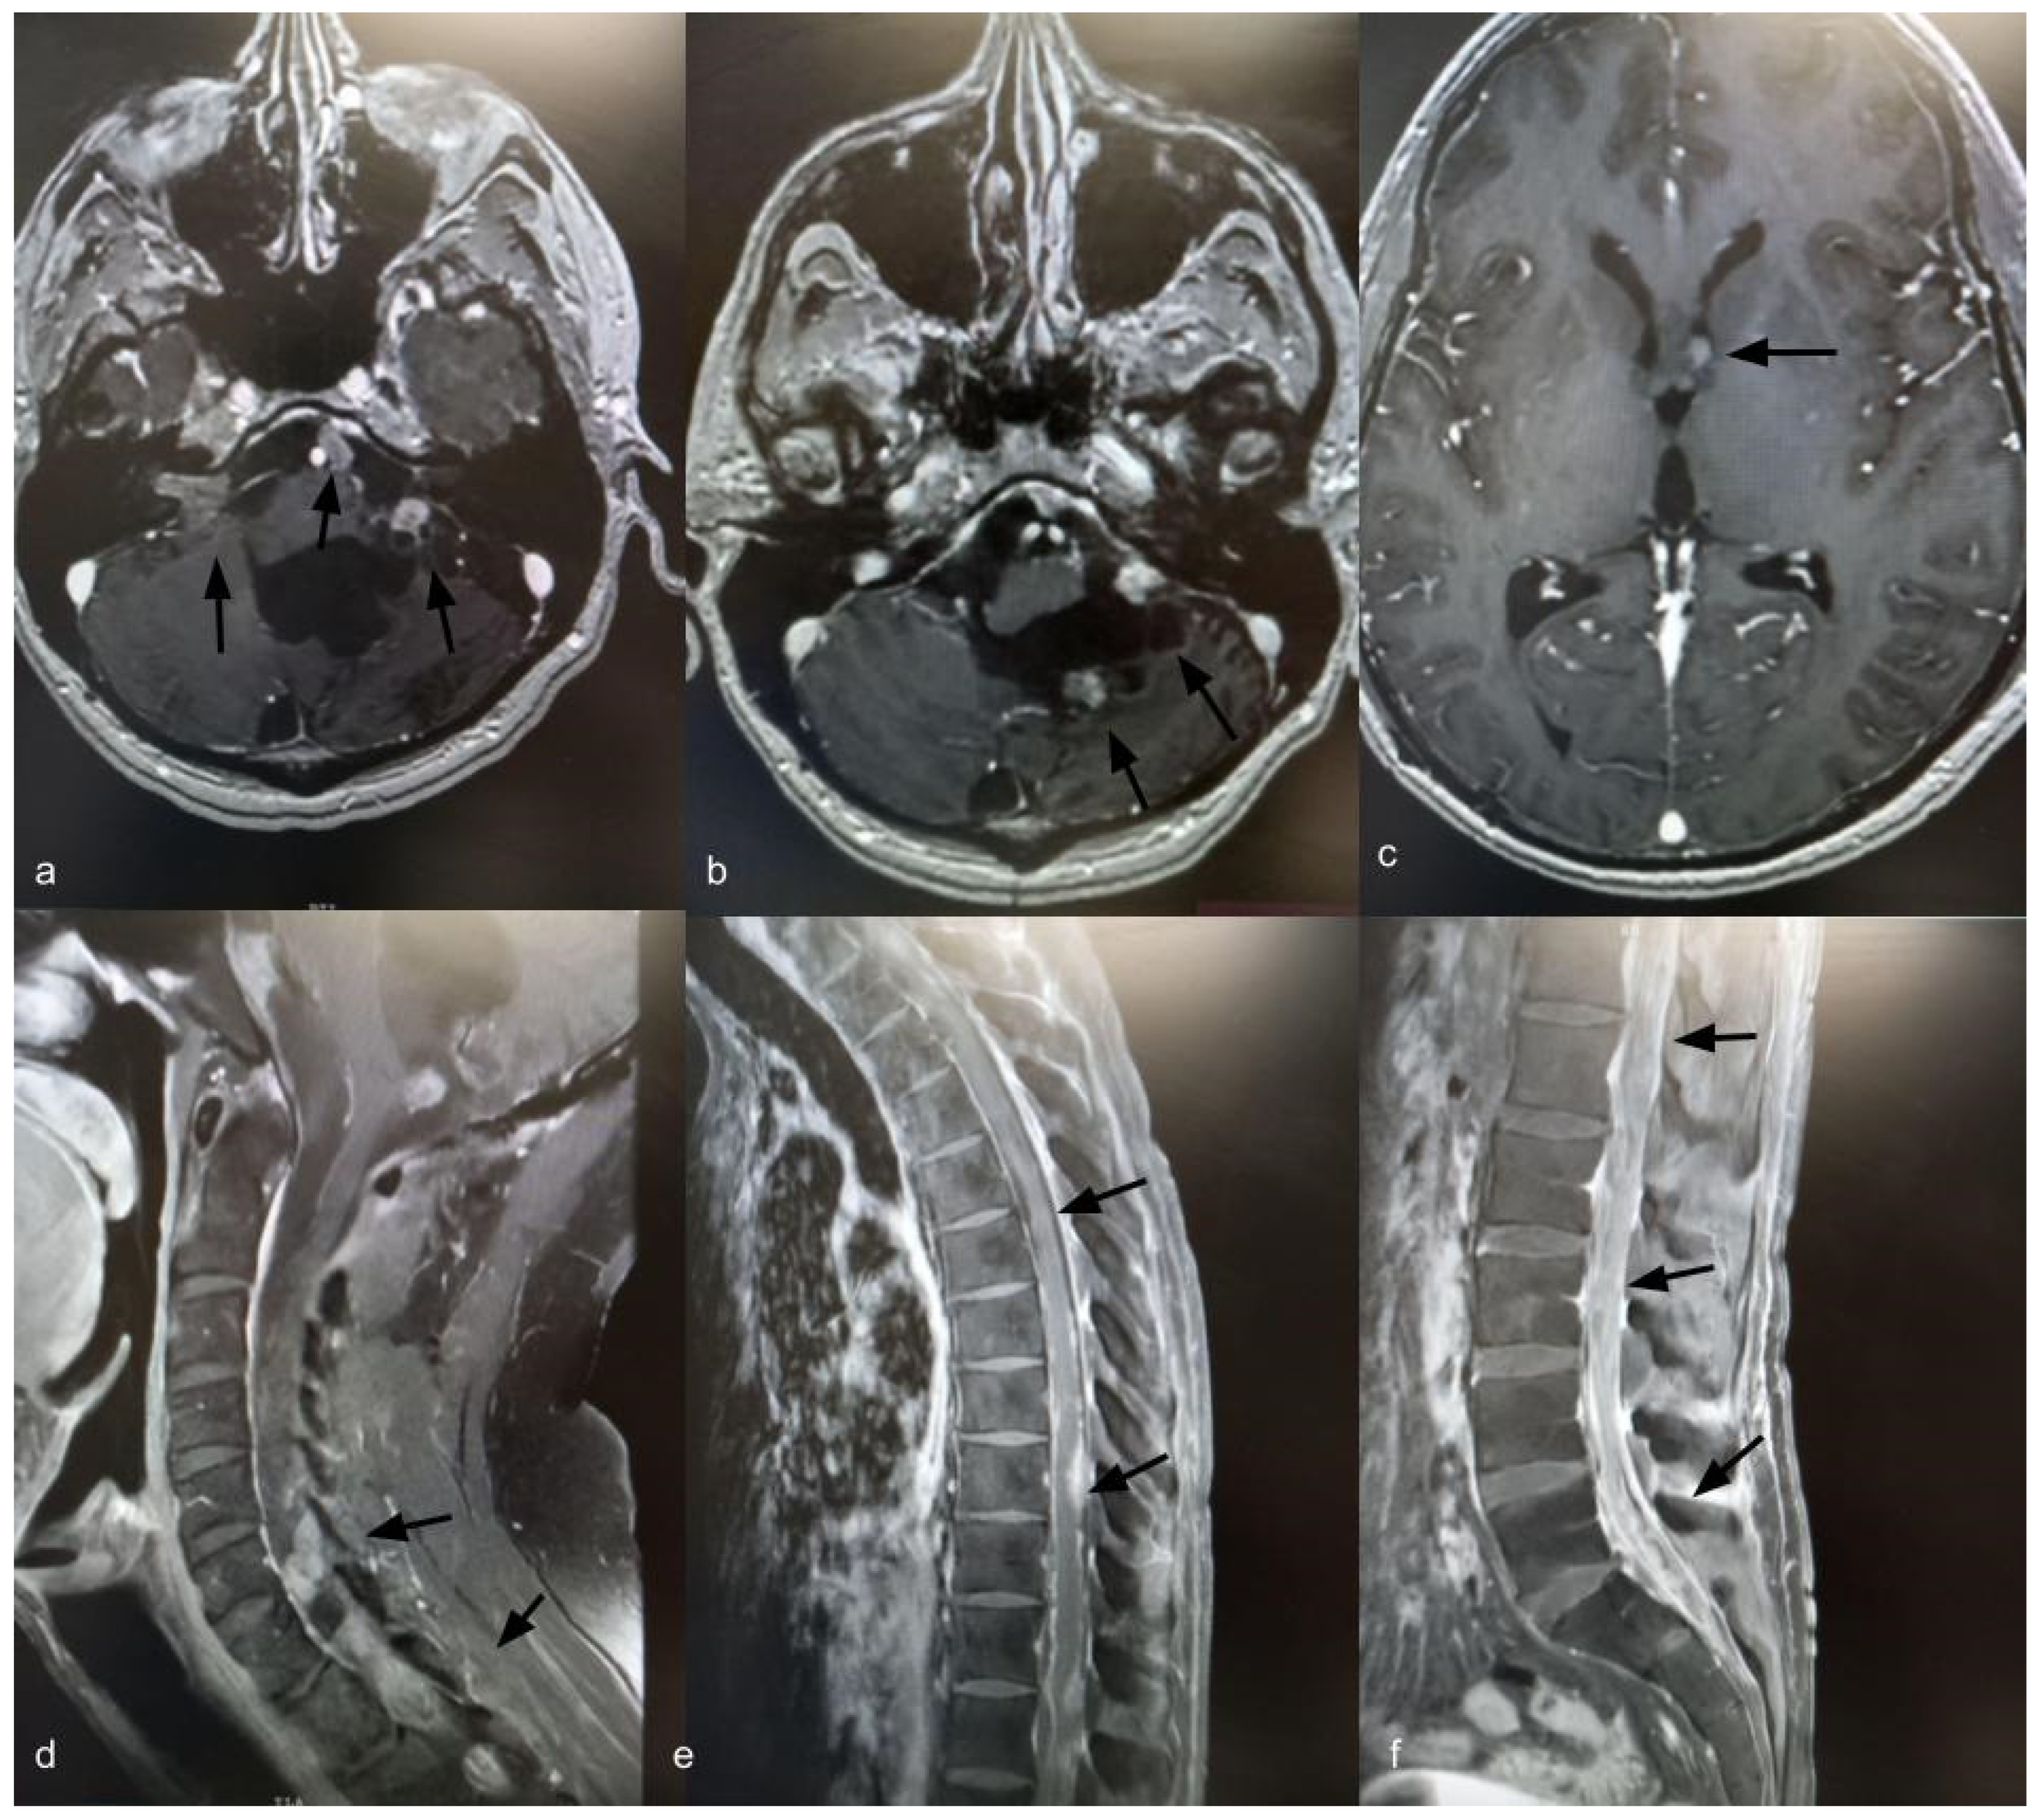

Fourteen years after the initial surgery, at age 40, the patient developed acute right-sided hearing loss. Brain and spinal MRI demonstrated multiple posterior fossa lesions, diffuse spinal leptomeningeal enhancement, and multiple solid lesions throughout the entire spine (Figure 3), consistent with LMD. Surgery was not pursued, as no clinical benefit was anticipated. The patient underwent craniospinal irradiation comprising 30 sessions. At the three-month follow-up, MRI showed stable disease. He subsequently developed symptomatic communicating hydrocephalus requiring ventriculoperitoneal shunt placement. CSF cytology was negative for neoplastic cells. Six months after radiotherapy, with no radiological improvement, systemic chemotherapy was initiated with carboplatin (600 mg), etoposide (175 mg), and vincristine (2 mg), administered every 28 days for six cycles. Thirty months after the diagnosis of LMD, the patient remains alive with stable brain and spinal lesions with no evidence of new disease (Figure 4).

Figure 4.

Axial T1-weighted brain MRI with gadolinium, 30 months after diagnosis of leptomeningeal dissemination, showing stable brain lesions (a–c) (indicated by black arrows). Sagittal T1-weighted spine MRI with gadolinium, 30 months after diagnosis of leptomeningeal dissemination, showing stable spinal enhancement and lesions (d–f) (indicated by black arrows).